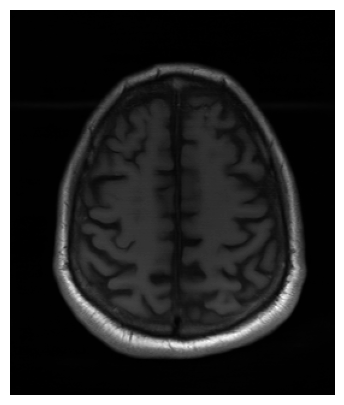

The visual inspection of the images reconstructed (available in Fig. 2) at acceleration factor 4 shows little to no visible difference with the ground truth original image. However, when increasing the acceleration factor to 8, we can see that smoothing starts to appear which leads to a loss of structure as can be seen in Fig. 3.

| T1 PSNR: 38.57 SSIM: 0.9348 | T2 PSNR: 37.41 SSIM: 0.9404 | FLAIR PSNR: 36.81 SSIM: 0.9086 | T1POST PSNR: 38.90 SSIM: 0.9517 |